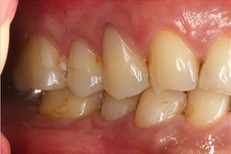

Intra-Oral Pictures (Before)